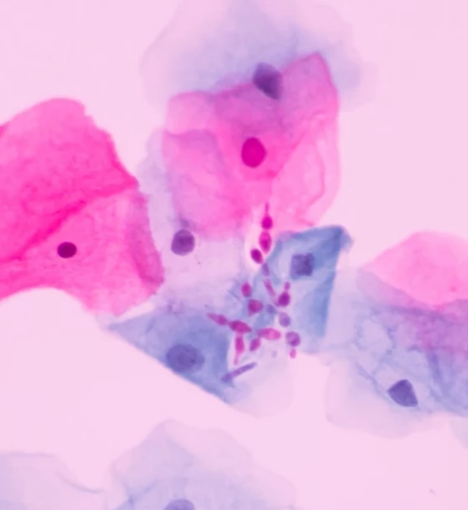

1. Candida albicans, PCR:

- يستخدم لاكتشاف عدوى الخميرة الناتجة عن الفطريات، والتي قد تكون سببًا للأعراض المهبلية مثل الحكة والاحتقان.

6. Human Papillomavirus (High Risk), PCR:

- يحدد وجود الأنواع عالية الخطورة من فيروس الورم الحليمي البشري، والتي يمكن أن تؤدي إلى تطور سرطان عنق الرحم.

11. Trichomonas vaginalis, PCR:

- يكشف عن طفيلي التريكوموناس، والذي يعتبر سببًا شائعًا للإصابة بالتهاب المهبل.